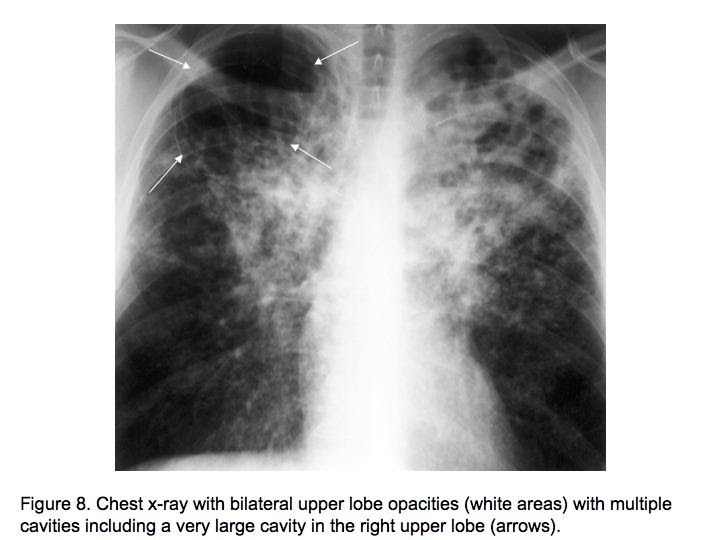

Pulmonary Tuberculosis Role of Radiology in Diagnosis and Management Sample X Ray Result With Tuberculosis The tb blood test and the tb skin test. Getty images (2) the likelihood that an. What to expect, results, and more. there are two types of tests for tuberculosis (tb) infection: A positive test result for tb infection. a positive test result for tuberculosis (tb) infection means you have tb germs in your body. tuberculosis (tb). Sample X Ray Result With Tuberculosis.